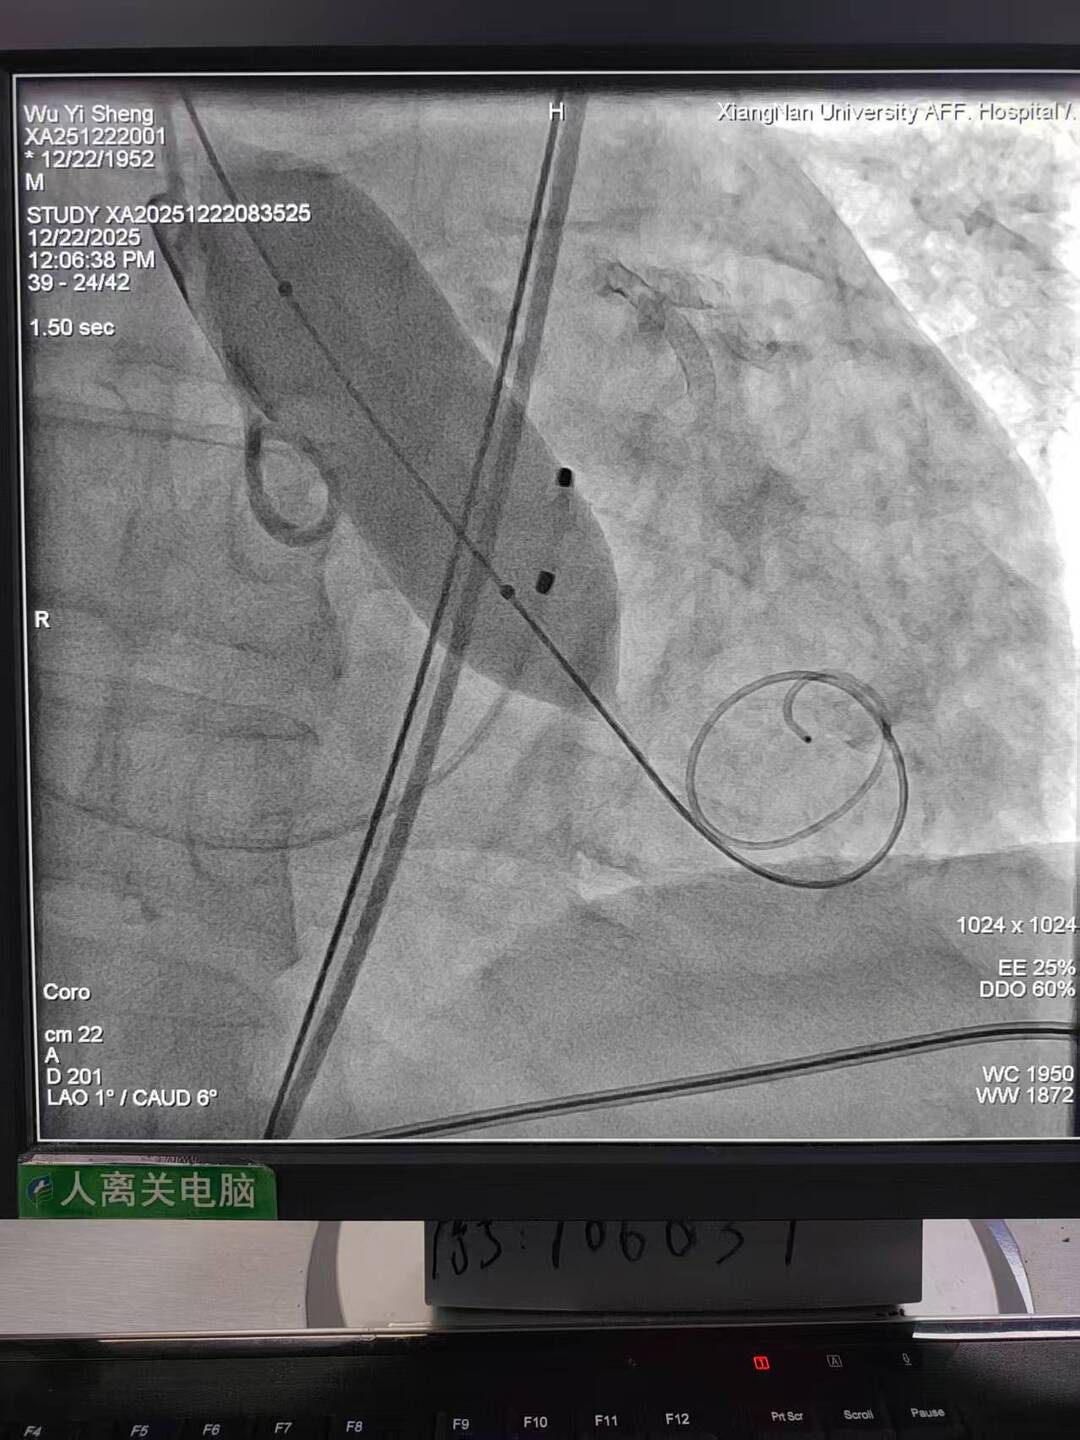

手术过程犹如在心脏内进行的“微雕”和“换门”工程,步骤环环相扣,每一步都考验着术者的技术功底与团队协作默契。术中,团队首先利用先进的可扩张血管鞘,在严重钙化狭窄的右侧股动脉腔内成功建立安全的手术通路;随后经该微创入路,先通过球囊扩张术为冠状动脉植入支架,快速恢复心肌血供;紧接着,在同一手术台、同一入路下,精准将人工主动脉瓣输送至病变位置并成功释放,顺利替换失灵的原生瓣膜。整个过程中,团队成功克服了外周血管入路困难的核心挑战,确保手术各环节无缝衔接、精准落地。